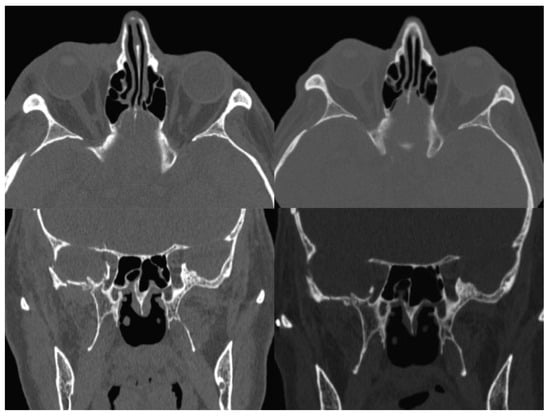

A new spiral craniomaxillofacial CT scan with coronal, sagittal, and three-dimensional (3D) reconstruction was performed the following morning. The imaging examination revealed a displacement of the lateral wall of the right SOF which was reduced in amplitude. The fracture was classified as a rare frontosphenotemporal fracture, according to Pellerin et al. [8], that is frequently associated with visual impairment (Figure 2). This pattern of fracture is characterized by the preservation of integrity of the lateral orbital wall and its whole dislocation. A thin layer of epidural blood of approximately 7 mm at the middle temporal fossa was also noticed, adjacent to the greater wing of the sphenoid bone.

Figure 2. 3D CT scan reconstruction showing four different projections of frontosphenotemporal Pellerin et al fracture pattern; note in frontal view (up right), SOF size reduction caused by medial displacement of the entire right lateral orbital wall; the black dashed line in the intracranial view (down right) shows the medial collapse of lateral orbital wall into the SOF. CT, computed tomography; SOF, superior orbital fissure; 3D, three-dimensional.